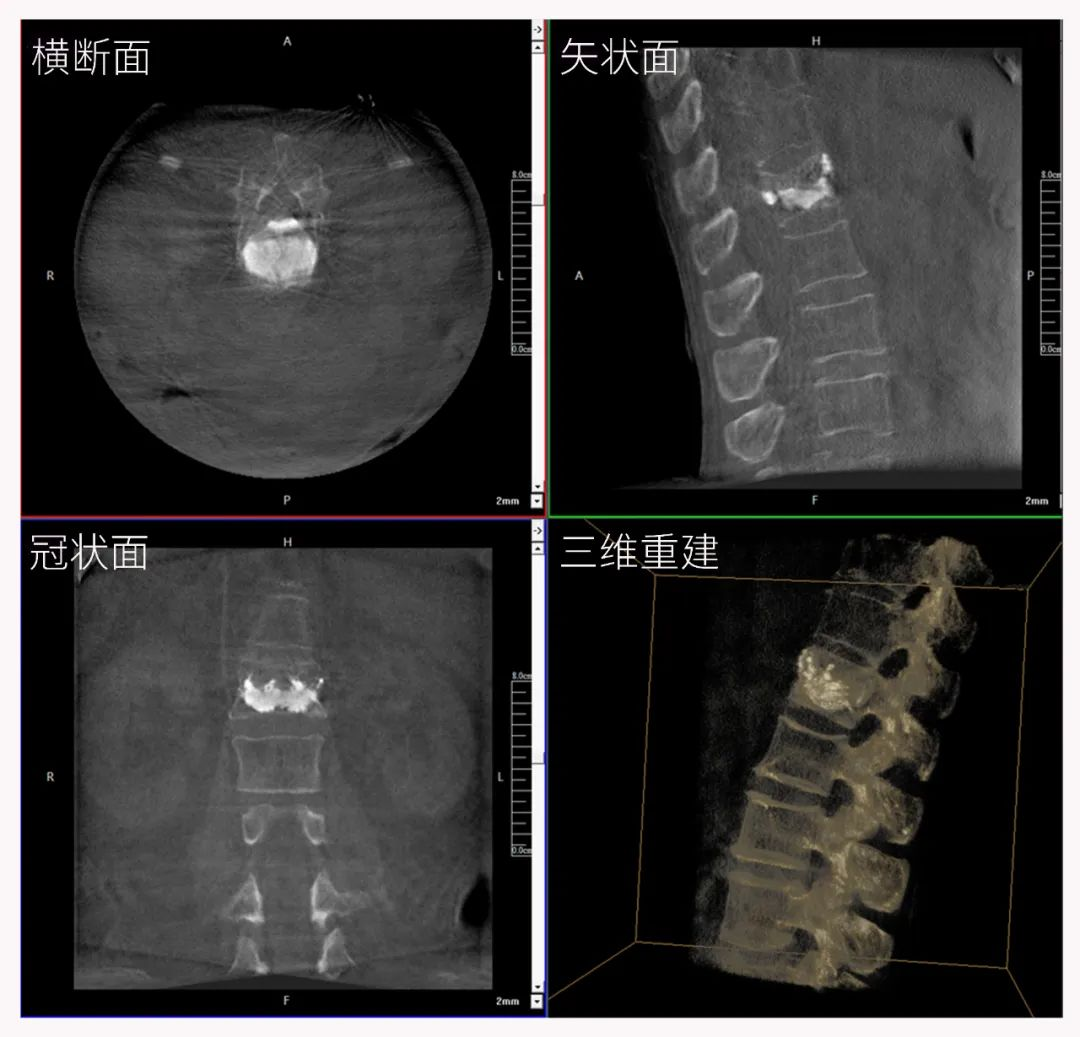

三維C形臂也被稱為“術(shù)中CT”,它具備二維C形臂的全部功能。此外,它還具備三維成像功能,三維C形臂旋轉(zhuǎn)采集多角度的二維投影數(shù)據(jù),再通過計(jì)算機(jī)進(jìn)行三維重建,能夠生成橫斷面、矢狀面、冠狀面斷層圖像以及三維立體圖像,提供更全面、更立體的解剖學(xué)信息。

三維“類CT”影像

病例3:超聲支氣管鏡下肺活檢(80歲)

三維C形臂還可以創(chuàng)新性地應(yīng)用在呼吸介入領(lǐng)域。例如,在經(jīng)皮穿刺或經(jīng)支氣管鏡肺結(jié)節(jié)活檢、定位、消融等場景中,用于確認(rèn)工具是否到達(dá)病灶、消融范圍是否完全覆蓋病灶等。

二維影像無法準(zhǔn)確判斷工具是否到達(dá)病灶

三維各切面影像都顯示工具達(dá)到病灶內(nèi)

二維C形臂提供的影像存在固有局限性,其成像原理是基于單一方位的投影,導(dǎo)致深部解剖結(jié)構(gòu)信息缺失,且容易受到骨骼和組織的重疊干擾,使得部分病灶難以清晰顯示,甚至被掩蓋。相比之下,三維C形臂通過三維重建技術(shù),可以獲得類似CT的斷層掃描圖像,從而解決了二維影像的重疊問題。

醫(yī)生能夠利用這些三維圖像,更直觀、更深入地分析病變,進(jìn)行全方位觀察,例如:精確評估骨折復(fù)位情況、清晰顯示內(nèi)植入物的位置及其與周圍組織的關(guān)系等。尤其在復(fù)雜骨折、脊柱手術(shù)、呼吸介入等臨床場景中,三維C形臂提供的詳細(xì)信息對手術(shù)導(dǎo)航和療效評估至關(guān)重要。